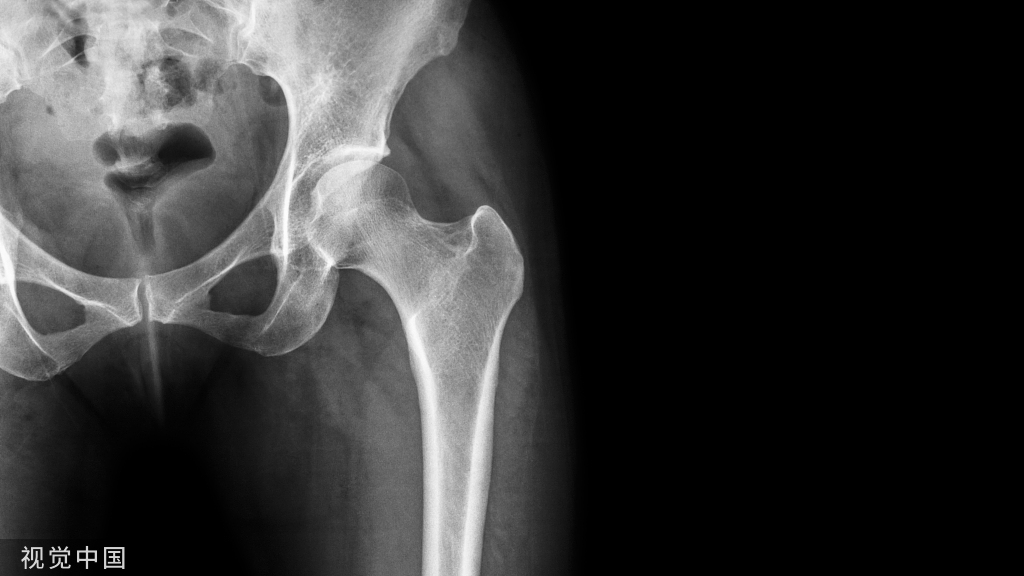

总结:对于广大患者来说,内固定物取出以后才能算是骨折治疗的真正结束。然而,我们如果想要取出内固定物,必须了解取出内固定物的效用和危险。取内固定物前必须进行影像学检查,确定骨折已经完全愈合,结合最新的影像学资料和病历了解内固定物的目前情况和位置。

在此解答文章开头案例中李小姐的疑惑:

主刀医生在给李小姐行腰椎椎弓根钉棒内固定手术治疗前,考虑到李小姐年龄较轻,所以术中并没有行大量椎板植骨融合;同时,术前李小姐的腰椎MRI(磁共振技术检查)显示伤椎椎间盘良好,并没有损伤,术中未行椎间融合术,所以愈合后需要拆除内固定物,否则内固定物的存在会影响腰椎的生物力学作用。

而苏阿姨是腰椎管狭窄症患者,不但进行了内固定,同时还做了节段融合术,所以其内固定物无须拆取,否则,会造成医源性的腰椎失稳。